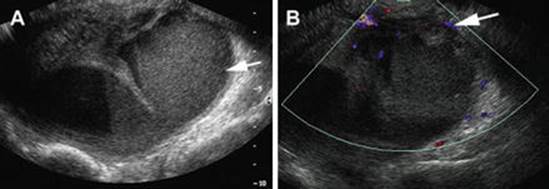

Fig. 4.11

Pyosalpinx. (a) Transvaginal ultrasound shows serpiginous tubular structure (arrow) in the adnexa with low-level internal echoes, consistent with pyosalpinx. (b) Color Doppler sagittal ultrasound image shows peripheral vascularity along the inflamed fallopian tube (arrow) (Reprinted from Chu et al. [66], with permission from Elsevier)